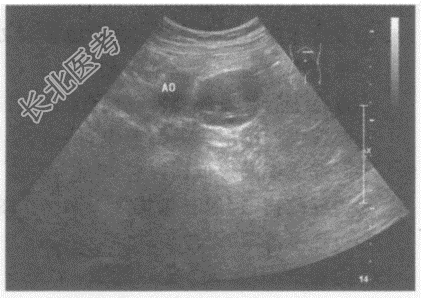

超声综合描述: 左肾下极与腹主动脉之间可见不均质低回声,与腹主动脉关系密切, 边界清晰,形态规则, 内可见形态不规则无回声,CDFI: 其内及周边均未见动静脉血流信号。见下图及彩图55。